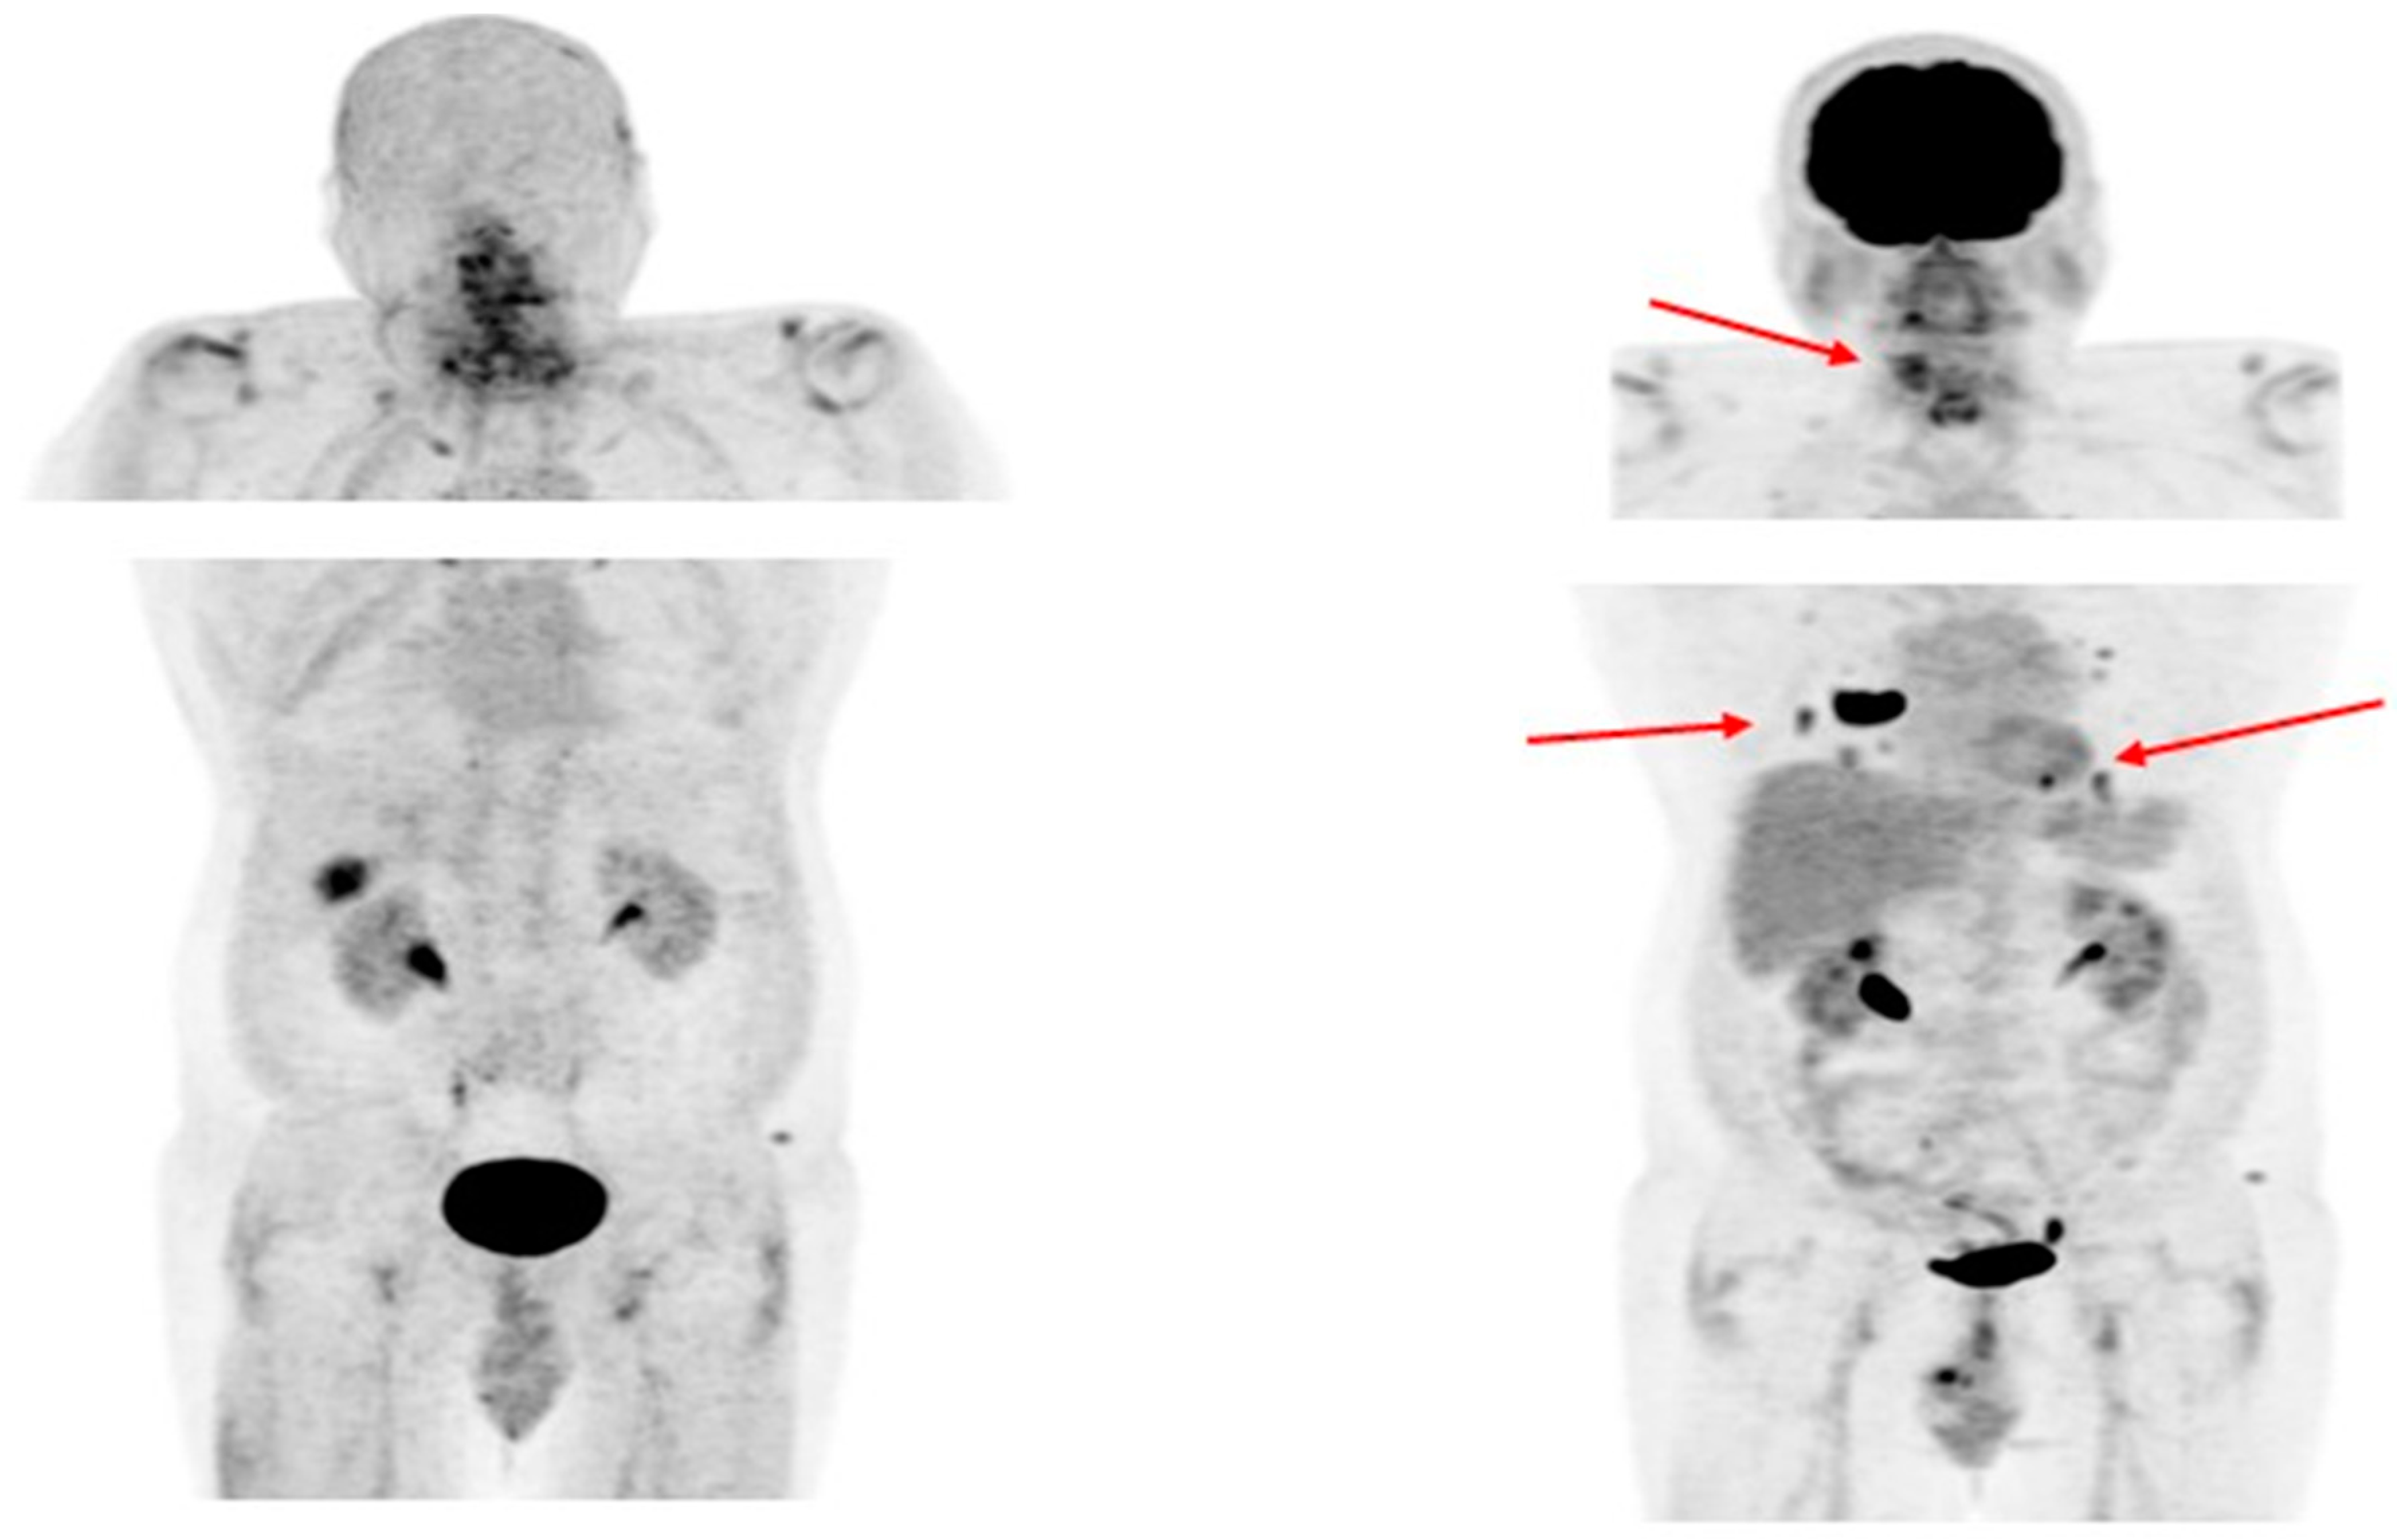

- Middendorp, M.; Selkinski, I.; Happel, C.; Kranert, W.T.; Grünwald, F. Comparison of Positron Emission Tomography with [(18)F]FDG and [(68)Ga]DOTATOC in Recurrent Differentiated Thyroid Cancer: Preliminary Data. Q. J. Nucl. Med. Mol. Imaging 2010, 54, 76–83. [Google Scholar]

- Vrachimis, A.; Stegger, L.; Wenning, C.; Noto, B.; Burg, M.C.; Konnert, J.R.; Allkemper, T.; Heindel, W.; Riemann, B.; Schäfers, M.; et al. [68Ga]DOTATATE PET/MRI and [18F]FDG PET/CT Are Complementary and Superior to Diffusion-Weighted MR Imaging for Radioactive-Iodine-Refractory Differentiated Thyroid Cancer. Eur. J. Nucl. Med. Mol. Imaging 2016, 43, 1765–1772. [Google Scholar] [CrossRef]